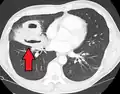

Description de cette image, également commentée ci-après

Tomodensitométrie (TDM) du thorax montrant une pneumonie bilatérale avec abcès, épanchements et cavernes. Homme de 37 ans.